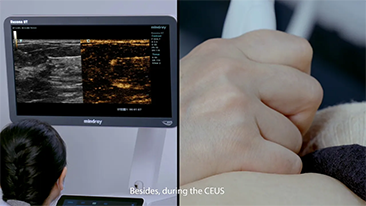

ImĂĄgenes generales

Las soluciones de imĂĄgenes generales de Resona de Mindray ayudan al personal clĂnico a realizar diagnĂłsticos y obtener resultados de tratamiento mĂĄs precisos y eficientes a travĂ©s de sondas para aplicaciones de subdivisiĂłn integrales y herramientas de aplicaciĂłn clĂnica eficientes.